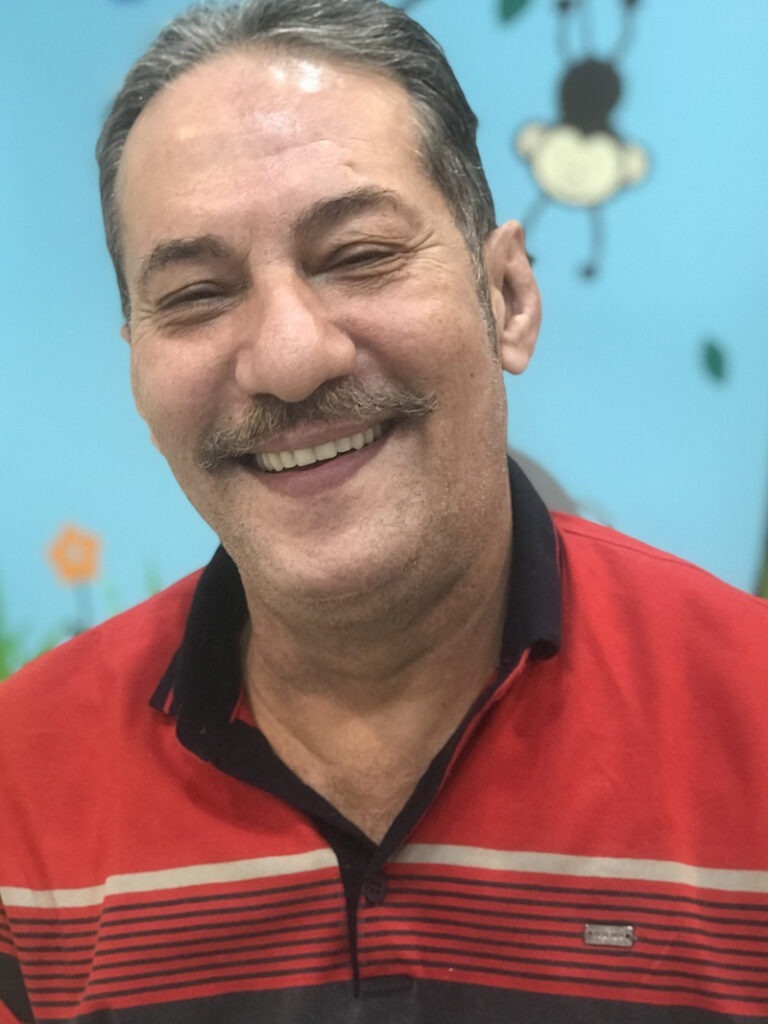

نمونه کارهای قبل و بعد از تحویل پروتز فک بالا دندان پزشکی رایان

قبل از تحویل پروتز فک بالا

بعد از تحویل پروتز فک بالا

بعد از تحویل پروتز فک بالا

نمونه کارهای تحویل پروتز دندان پزشکی رایان